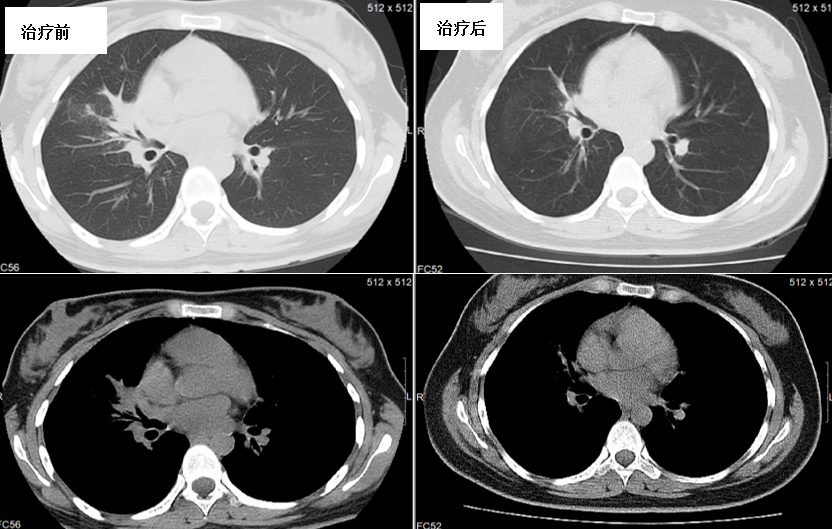

胸部CT(图2):右肺及左下肺阴影,右肺为主,纵隔、右肺门淋巴结肿大。

图2. 治疗6个月后右肺病灶较前减少